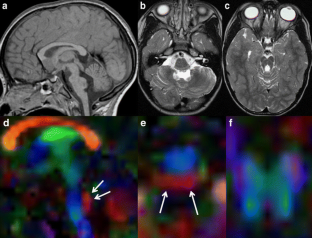

Fig. 3